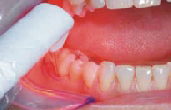

Onemocnění parodontu patří ke druhému nejčastějšímu onemocnění v dutině ústní, ihned po zubním kazu. Nejčastějším problémem je gingivitis- zánět dásní a také parodontitis - zánětlivé onemocnění postihující závěsný aparát zubů, přilehlou dáseň i kost. Mezi časné projevy gingivitidy patří krvácení dásní, které může v případě parodontitidy přejít ve tvorbu parodontálních chobotů, spojené se zápachem z úst, tvorbou hnisu, bolestmi a viklavostí zubů v důsledku ztráty kosti. Tomuto onemocnění se dá úspěšně předcházet pravidelnými kontrolami, sanací chrupu a péčí v rámci dentální hygieny.

Přístroj na principu světlem aktivovaná desinfekce neboli fotodynamická antimikrobiální chemoterapie. Přístroj s okamžitým účinkem ničí veškeré mikroorganismy bez jakýchkoli vedlejších účinků. Jedná se o bezbolestné ošetření, které nevyžaduje anestezii, nemá vedlejší účinky a ničí 99% bakterií. Používá se především v parodontologii a implantologii při léčbě zánětů v okolí zubů a implantátů (dezinfekce tzv. chobotů), záchovné stomatologii (ošetření kazů) i endodoncii (dezinfekce kanálků zubu).